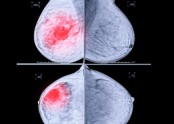

- 소요시간 : 10분 내외비용 : 1.5만원(보험 적용) - 4.5만원(보험 미적용) ● 유방촬영을 하는 이유는 유방의 패턴을 지방성과 치밀유방으로 분류하고, 암의 소견인 미세 석회화와 혹를 찾기 위해서 입니다. …

- 유방에는 아무런 멍우리가 만져지지 않아도 단지 정기 검진 목적으로 시행한 유방 사진 촬영에서는 석회화가 보이는 경우가 자주 있습니다. "석회화"(calcification)"란 유방 사진 촬영에서 유방조직 내에 조개 껍질 같은 칼슘 성분으로 된 미세한 석회질이…

- ▶ 정기 검진중 미세 석회화가 발견되었다고 합니다.

- ■ 정기적으로 유방촬영하는 것이 왜 중요할까요? ① 아래 환자분은 30대 중반에 검진상 양성 석회화가 있던 분으로 5년 되던 40세에 국가암 검진을 했고, 이때 과거에는 보이지 않던 소견으로 유방촬영 하부 작은 부위에 …